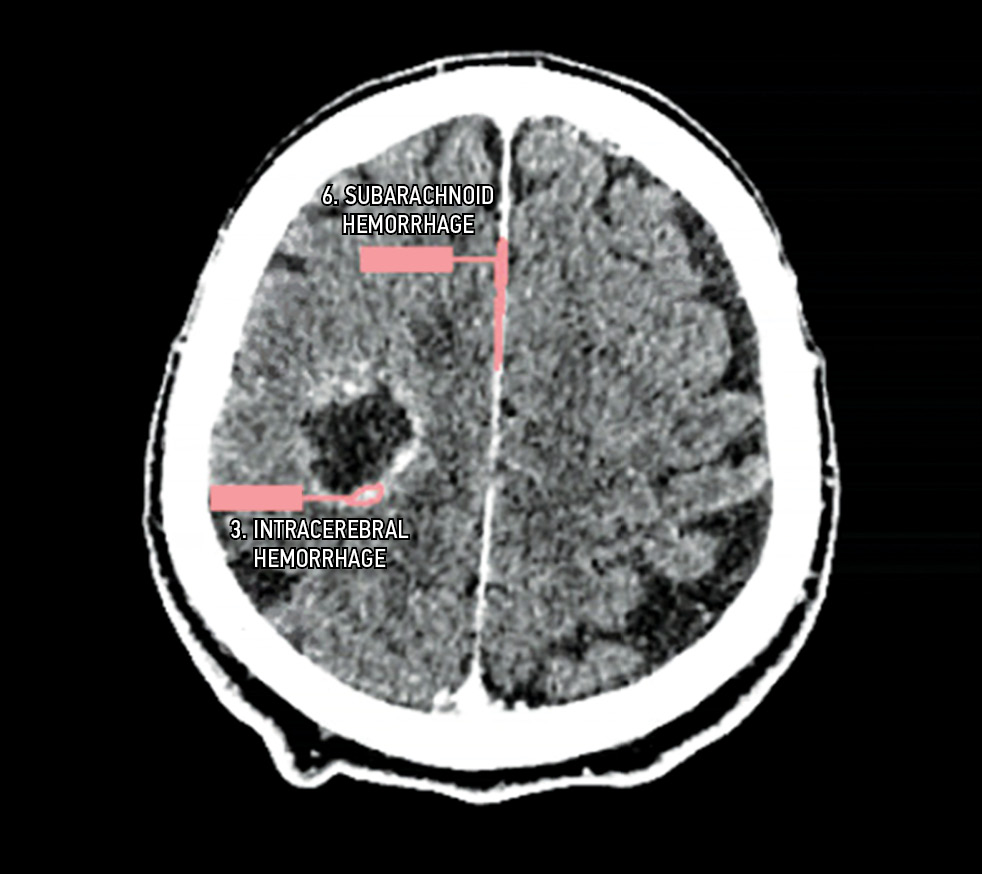

Fig. 5. Defect: an incorrect series was evaluated (contrast-enhanced computed tomography instead of native on). Modality: computed tomography.

Fig. 6. Defect: off-target markings, contrast-enhanced computed tomography instead of native computed tomography. Modality: computed tomography.

- Defects that affect the safety of patients and work of HCPs: failure to implement functions declared by the manufacturer; comments that influence a radiologist or complicate their work; and irreversible damage to original research data. This group includes, for example, Group D (D2, D3, D4) and F defects. Separately, a D7 defect (absence of a warning label “For research/scientific use only”) should be considered. This defect can only occur in the research setting and can never occur when using AI-based software as a medical device.

- Defects that do not affect the safety of patients but affect the work of HCPs: functional defects that do not conform to generally accepted standards for the presentation of research interpretation results. This group includes Group E and C (C1, C2, C3) defects.

- Defects that affect the safety of patients and work of HCPs: Group C defects (C1, C2, C3) and D4 and D5 defects.

- Defects that do not affect the safety of patients but affect the work of HCPs: Group E and D defects (D1, D2, D3).